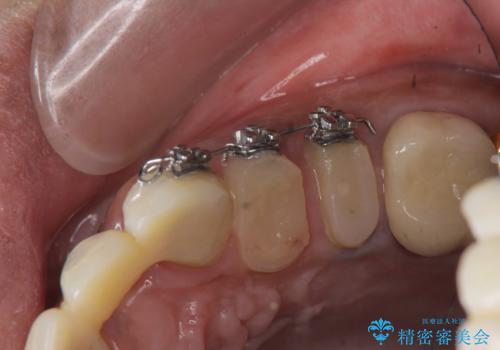

なお左上4に関しては縁下歯質を改善するため、歯冠挺出を行っております。

歯冠延長術について

歯冠長延長術とは歯肉弁根尖側移動術とも言い、歯の高さが低くクラウン(被せ物)による治療が難しい場合に、歯茎を歯根方向に下げることで歯の高さを確保する手術です。歯の高さが十分にあることで、外れにくいしっかりとしたクラウンを被せることができます。